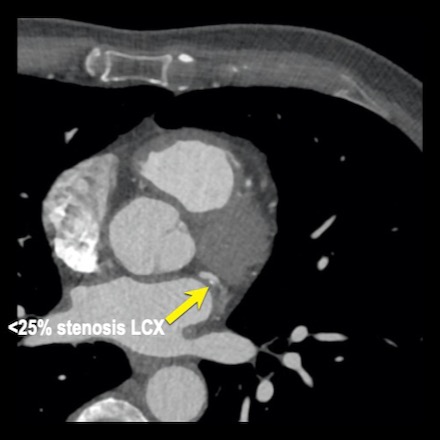

case 1 – CAD-RADS 2/P1

First, scroll through the scan.

Not all images are included. Some images without any abnormalities are skipped

from the series.

How would you describe the findings on the coronary CTA?

The findings are:

- Agatston score of

this patient was 14 (P1). Please, also note the calcification of the aortic valve. - Some partially

calcified and calcified plaques are present in the LAD with mild stenosis

(25-49%). - Calcified-plaque in

the LCX causing minimal stenosis (<25%). - Non-calcified

plaque in the distal RCA causing minimal stenosis (<25%). - This patient classifies

as CAD-RADS 2/P1, which means no further workup is needed.